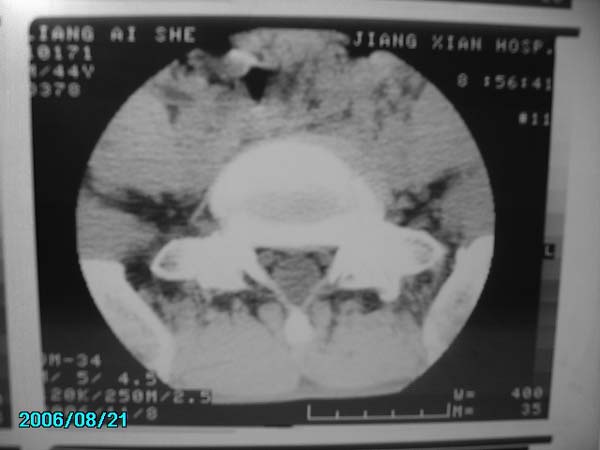

男,40岁,腰疼半年

l5-s1右侧后突出

腰椎侧弯,l4-5椎间盘膨出。

腰4-5、腰5-骶1椎间盘后缘变平直,可考虑椎间盘轻度突出。余未见异常

部分层面有轻度彭出。